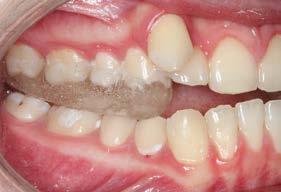

Figura 3. Lateral derecha. Figura 4. Izquierda de inicio. Figura 5. Frente. Figura 6. Overjet, laterales derecha e izquierda.

Las fotografías intraorales muestran las relaciones molares clase II y las relaciones caninas clase II bilaterales (Figura 3 y 4), espaciamiento anterosuperior, un overjet y overbite aumentado (Figura 5). La forma de los arcos es cuadrada, superior e inferior, con el apiñamiento moderado inferior y los espacios en superior.